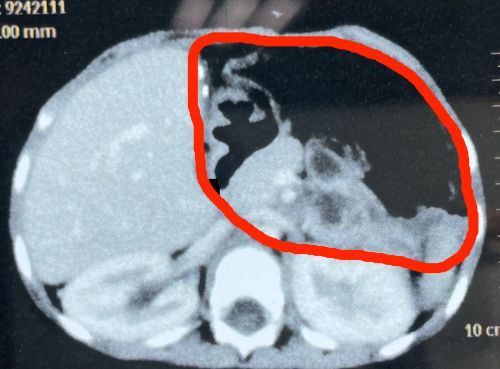

术前ct可见:肝脏上有一个巨大肿瘤。

术后ct显示,肝脏肿瘤已切除干净。